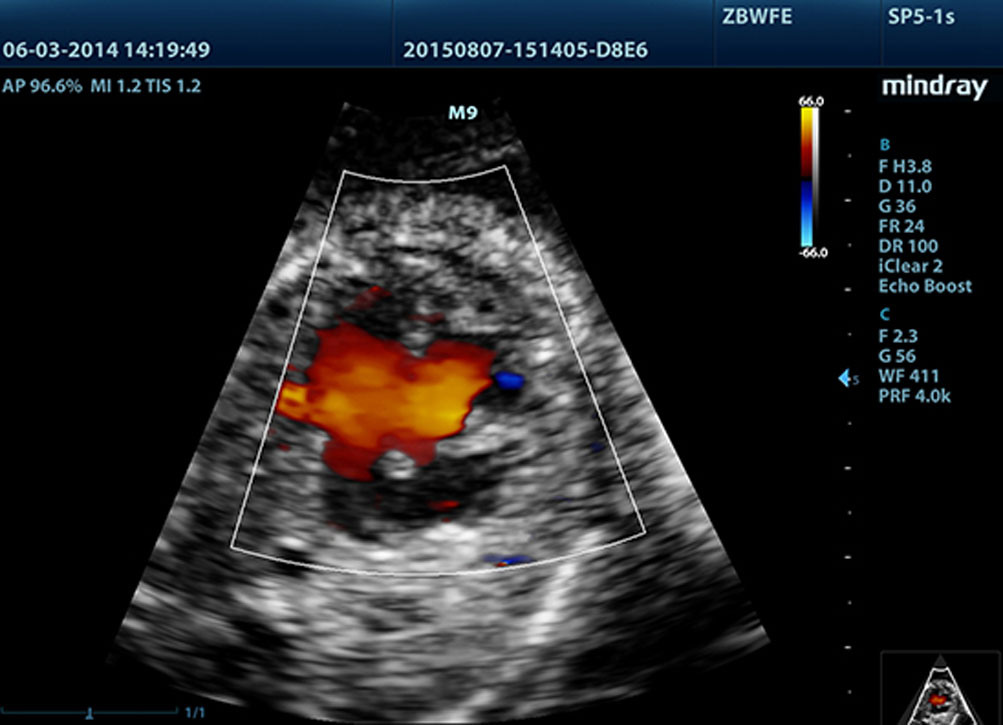

G?owice z zastosowanymi technologiami 3T i Single Crystal (pojedyÅczy kryszta?)

Technologie dostarczaj?ce ostrzejsze obrazy - wszystkie sondy kompatybilne z M9 s? wyposa?one w unikaln? technologi? 3T Firmy Mindray. Dodatkowo technologia Single Crystal (pojedynczego kryszta?u), oferuje lepsz? penetracj? i dynamiczny obraz przep?ywu w trybie Dopplera Kolorowego, zw?aszcza podczas skanowania trudnych przypadkÃģw.